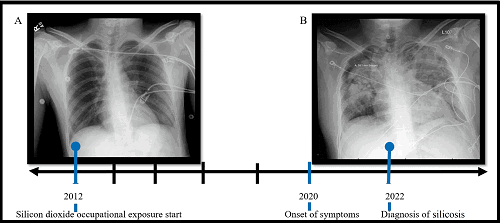

Chest x-ray transition showing accelerated silicosis, with image (A) showing the chest X-ray 10 years prior and (B) the chest X-ray at the time of diagnosis. Photograph: From an article by Patino S, Izquierdo-Pretel G (July 05, 2022) A Case Report of Accelerated Pulmonary Silicosis